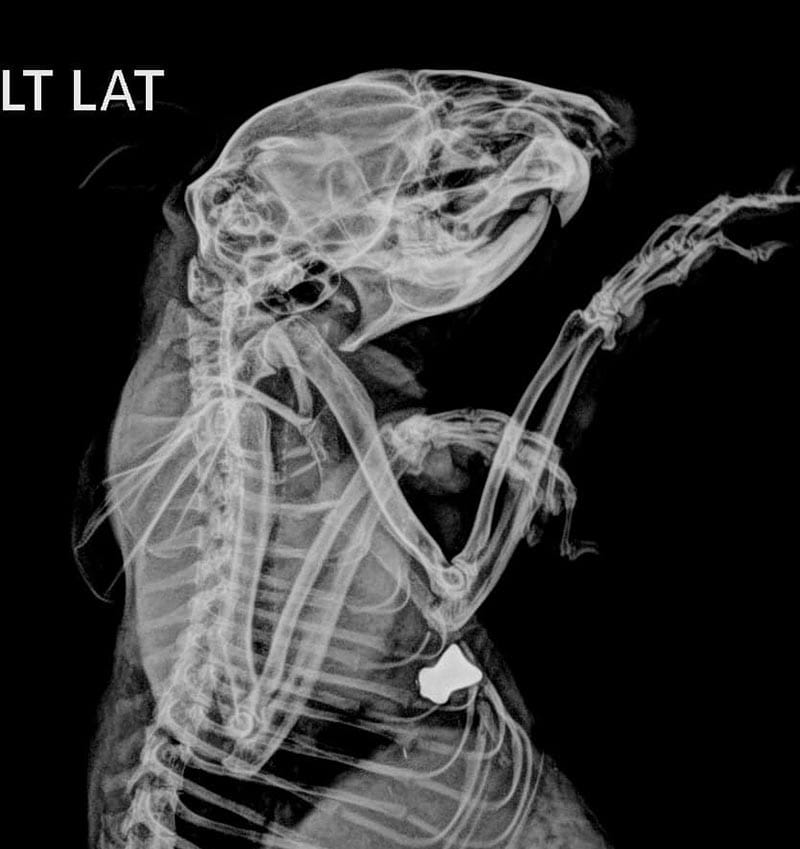

El cuerpo presentaba pérdida de fuerza y problemas respiratorios, en las placas se observó que le fueron disparados dos diábolos los cuales ya tenían tiempo en su organismo, sus huesos femorales estaban afectados así como su cadera.

En un procedimiento se los retiraron y detectaron que eran de plomo y generan intoxicaciones, por lo que el animalito estaba en tratamiento.